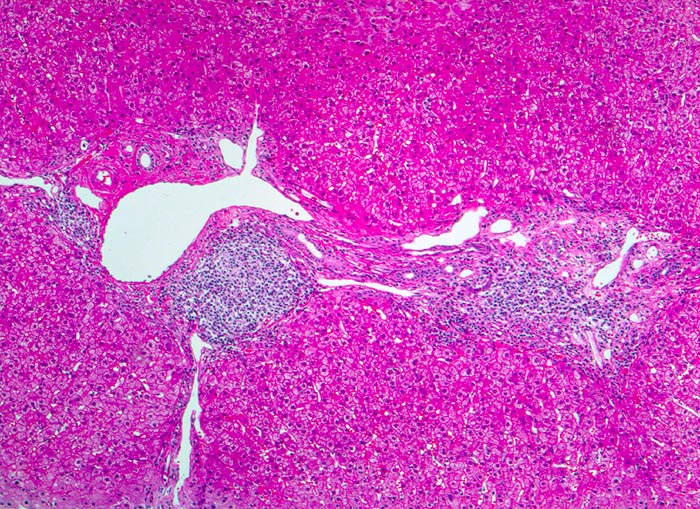

chronische Hepatitis C mit geringgradiger Aktivität und Fibrose

Dichtes lymphoides Infiltrat in den Portalfeldern mit Ausbildung eines Follikels. Stellenweise greift die Entzündung auf das angrenzende Parenchym über ( periportale Hepatitis). Zwischen den fibrosierten Portalfeldern verlaufen bindegewebige Septen.

Die Ausbildung von Lymphozytenaggregaten in Form von Follikeln in den Portalfeldern ist typisch aber nicht pathognomonisch für die chronische Hepatitis C.